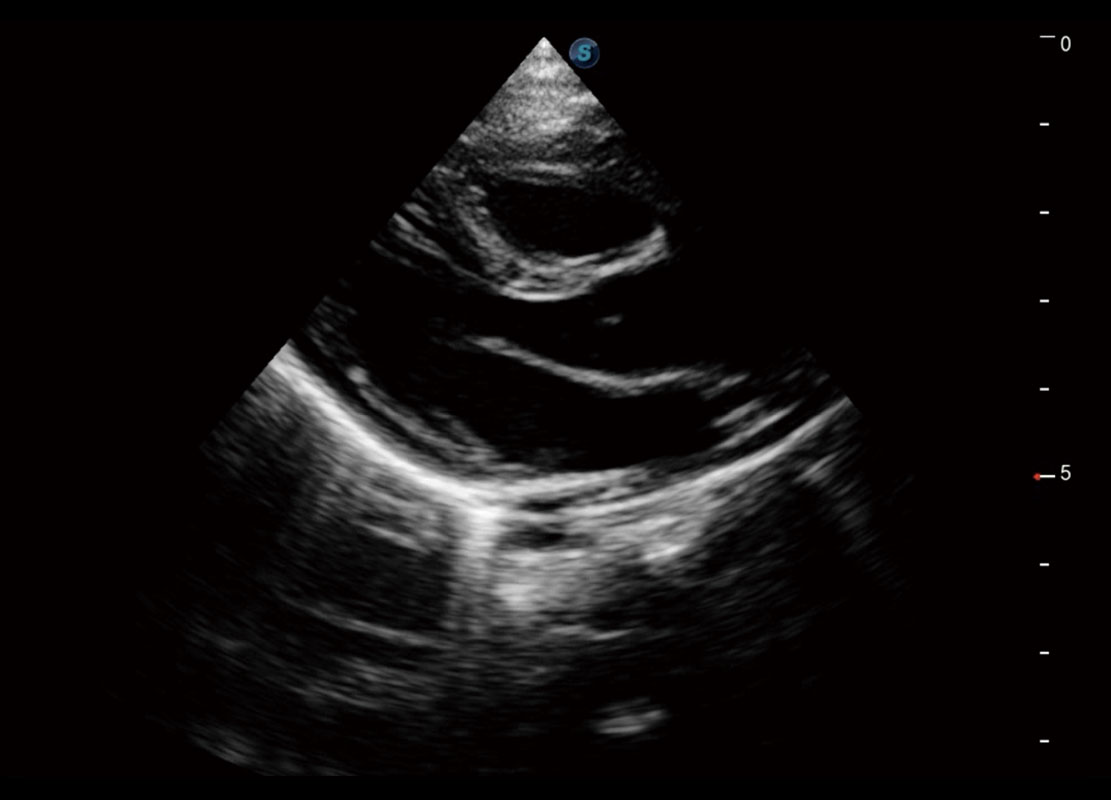

P60搭载一系列胎儿心脏成像技术,实现精细的胎儿心脏评估。

右室双出口